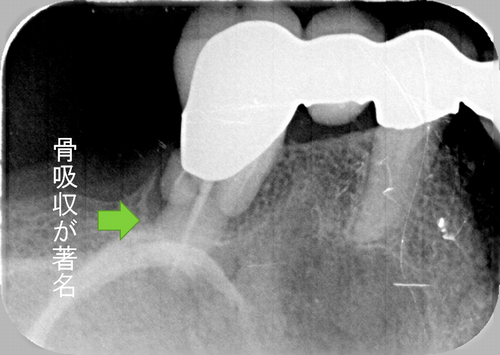

この患者様は、右上の奥歯の歯茎から出血してくるとのことで来院されました。歯周組織検査とレントゲンで診断を行った結果、重度の歯槽膿漏が認められ、保存不可能の為、抜歯になると伝えたところ、入れ歯は絶対に嫌だと言われたので、インプラント治療となりました。CT撮影を行ったところ、上顎洞底までの距離が3ミリ程度しかなかったのですが、骨が固く、フィクスチャーの一次固定が良好だったので、開窓法による上顎洞底挙上術とフィクスチャーの埋入を同時に行いました。約10カ月後に二次手術を行い、上部構造をセットしました。また、右下の臼歯部のブリッジにも大きな二次カリエスが認められ、7番の遠心根が抜歯になり、6番、7番にインプラント治療をしました。